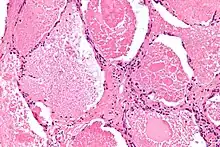

| Micrograph of pulmonary alveolar proteinosis, showing the characteristic airspace filling with focally dense globs referred to as chatter or dense bodies. H&E stain. | |

Lung washings or tissue for histopathologic analysis are most commonly obtained using bronchoalveolar lavage and/or lung biopsy.[12] Characteristic biopsy findings show filling of the alveoli (and sometimes terminal bronchioles) with an amorphous eosinophilic material, which stains strongly positive on PAS stain and the PAS diastase stain. The surrounding alveoli and pulmonary interstitium remain relatively normal.[13] Electron microscopy of the sample, although not typically performed due to impracticality, shows lamellated bodies representing surfactant.[14] An alternative diagnosis with similar histomorphologic findings is Pneumocystis jirovicii pneumonia.[14]

Lung washings characteristically yield a fluid which is "milky"composition. Under the microscope, samples show 20-50 micrometer PAS-positive globules on a background of finely granular or amorphous PAS-positive material. There is typically a low numbers of macrophages and inflammatory cells (although this is variable).[13][14]